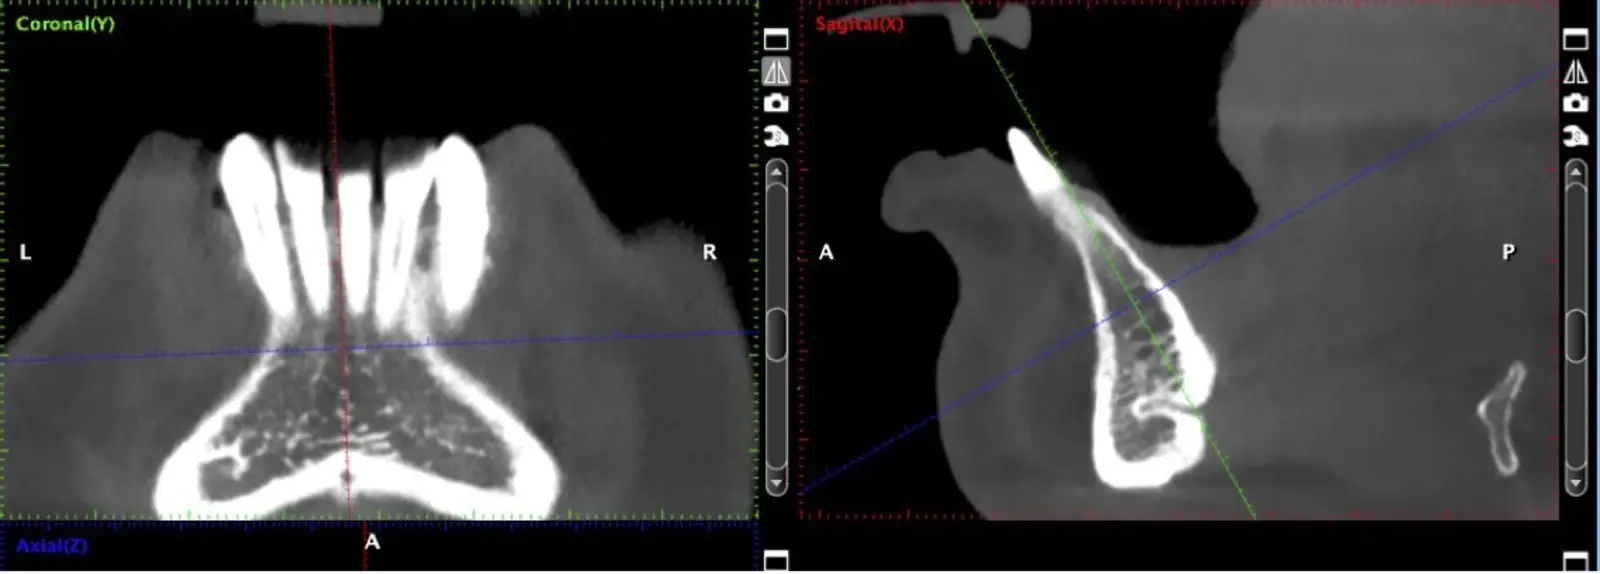

El uso de vibraciones ultrasónicas se introdujo por primera vez hace dos décadas para superar las limitaciones de la instrumentación tradicional.12,13 Altiparmak y cols.14 reportaron en su estudio que la cirugía piezoeléctrica redujo significativamente la incidencia de alteraciones sensoriales tanto de la piel como de la mucosa oral, y redujo también el daño pulpar en los dientes adyacentes, sobre todo en los injertos sinfisiarios.

La osteotomía con insertos de piezoeléctrico nos permite un corte más definido con menor pérdida de hueso residual, ya que los insertos son extremadamente finos.